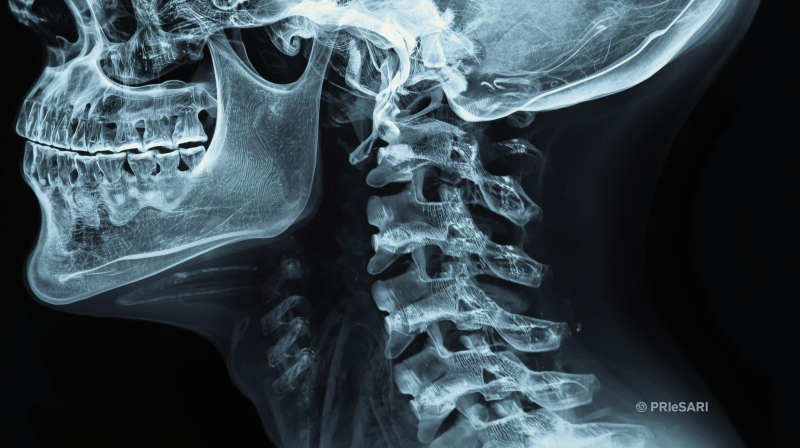

6. 주의해야 할 증상

- 목 뒤가 단단하게 굳고 색이 변한다

- 손·팔 저림, 수면장애, 만성 두통까지 나타난다

👉 이미 진행된 단계일 수 있으므로 X-ray, MRI 검사로 정밀 진단 필요